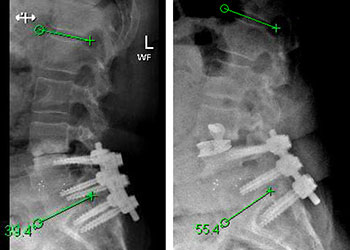

Back:

Revision Surgery Treats Intractable Neck Pain & Cervical Deformity

Author: Benjamin R. Cohen M.D., F.A.A.N.S., F.A.C.S., Read More!